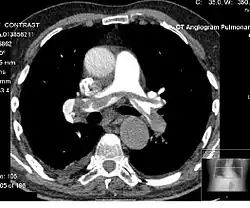

Angiography

Example of a CTPA, demonstrating a saddle embolus (dark horizontal line) occluding the pulmonary arteries (bright white triangle)

Computed tomography angiography (CTA) is a type of contrast CT to visualize the arteries and veins throughout the body.[47] This ranges from arteries serving the brain to those bringing blood to the lungs, kidneys, arms and legs. An example of this type of exam is CT pulmonary angiogram (CTPA) used to diagnose pulmonary embolism (PE). It employs computed tomography and an iodine-based contrast agent to obtain an image of the pulmonary arteries.[48][49][50] CT scans can reduce the risk of angiography by providing clinicians with more information about the positioning and number of clots prior to the procedure.[51][52]